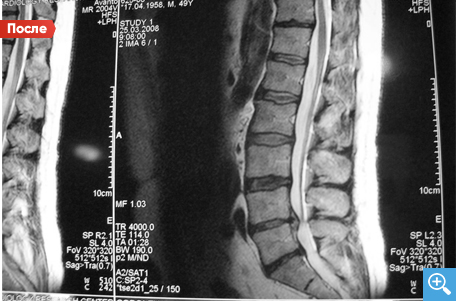

До Детензор-терапии

После Детензор-терапии

Секвестрированная грыжа

После 6 месяцев Детензор-терапии по одному сеансу 1 раз в день по 45 минут отмечается очевидный регресс секвестрированной грыжи межпозвонкового диска с 6,7 мм до 2,8 мм